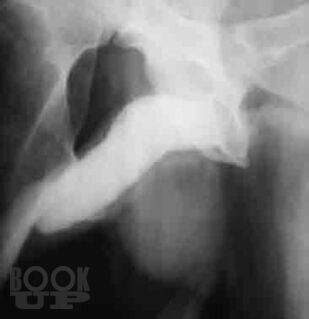

В руководстве представлены общепринятые и новейшие технологии диагностики и лечения актуальной проблемы уроандрологии – веногенной эректильной дисфункции. Подробно описаны методики традиционных общеклинических, ультразвуковых и рентгеновских методов обследования, а также дополнительных методов диагностики – компьютерной и магнитно-резонансной томографии, лазерной флоуметрии. Обоснована эффективность консервативного медикаментозного лечения и возможность использования экстракорпоральной ударно-волновой терапии. Описаны традиционные хирургические операции, а также альтернативные микрохирургические и рентгенэндоваскулярные вмешательства. Представлена патоморфологическая характеристика структурно-функциональных изменений полового члена у больных с веногенной эректильной дисфункцией. Доказано наличие варикозной болезни органов малого таза и ее влияния на мужское здоровье. В приложении собраны все необходимые диагностические тесты – опросники для пациентов.